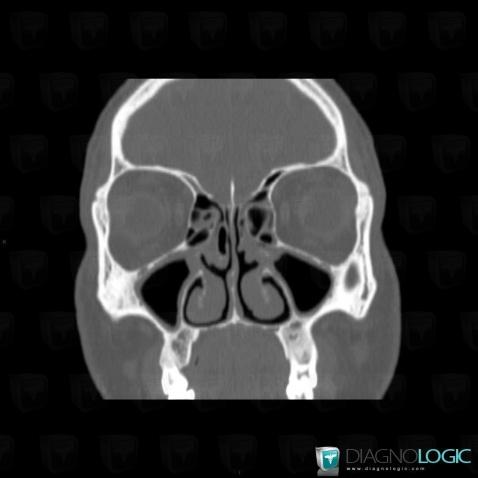

- Diagnostic Polypose naso sinusienne, Localisation(s) Sinus, comportant les gammes Masse intra sinusienne, Comblement sinusien